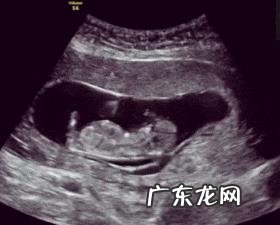

怀孕四个月,胎儿发育的五脏俱全,五官清晰可辨,此时的胎儿已经有12厘米高,150克重了,看起来像个中等大小的梨 。现在的胎儿浑身覆盖了一次软软的胎毛,可以握紧拳头、皱眉头,还能吸吮自己的手指玩,而且能够打嗝了,对于光照,此时的胎儿也有了一定的感知能力 。

胎儿的胎动最早开始于孕8周左右,只是那个时候的胎儿太小,动作幅度也不明显,所以准妈妈不会有什么感觉 。但是到达孕4月,胎儿的胎动逐渐会被准妈咪感知 。